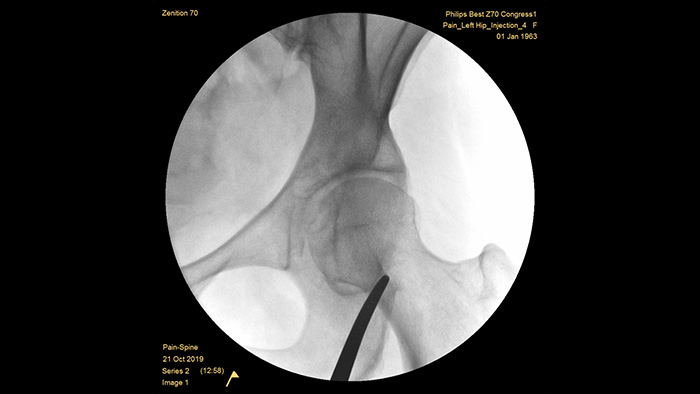

За более чем 50 лет разработки систем с мобильными C-дугами для хирургических кабинетов Philips заработала репутацию за выдающиеся достижения в области визуализации и эффективности дозы. Наши мобильные решения для хирургии Zenition основаны на комплексном подходе к управлению дозовой нагрузкой. Они обеспечивают необходимое качество изображения во время инвазивных процедур для лечения болевого синдрома, а также эффективно управляют дозовой нагрузкой на пациентов и медицинский персонал.

Уникальная предустановленная настройка для исследования болевого синдрома позволяет пользователям без труда выполнять настройку системы при проведении интервенционных процедур, направленных на лечение болевого синдрома.

В отличие от других систем без функции удаления шумов от металлических объектов, MetalSmart автоматически исключает металлические артефакты, вызванные наличием металлических имплантатов, чтобы обеспечить более высокое качество изображения и эффективный контроль дозы при проведении процедур, направленных на лечение болевого синдрома, а также при исследовании пациентов с металлическими имплантатами. BodySmart способствует получению правильных изображений и значений эффективности дозы с первого раза, автоматически адаптируя область измерения к исследуемой области.

Оптимальная глубина полностью уравновешенной С-дуги обеспечивает достаточно места для размещения вокруг пациентов с лишним весом и позволяет получать изображения поясничного отдела позвоночника и тазобедренного сустава. Она поддерживает позиционирование над столом даже для столов с большим основанием.